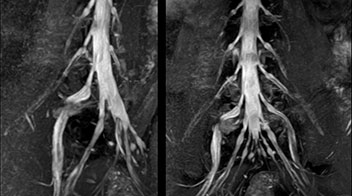

“In such case, we would then browse through axial T2-weighted MR images slice by slice and mentally reconstruct the actual situation based on both radiculography and MRI. Fortunately, NerveVIEW can now very well show nerve courses and presence of nerve compression or edema in one single image series.” “We have often seen NerveVIEW directly depict details of the nerve compression that were not observed by radiculography. Therefore, we think that with NerveVIEW we can reduce the number of invasive examinations, especially for some patients with lumbar plexus symptoms.”

“Before NerveVIEW, diagnosis by MRI alone was sometimes difficult, unless there was a strong suspicion based on clinical symptoms,” says Shoji Yabuki, MD, DMSc, Orthopedic surgeon at Fukushima Medical University School of Medicine. “This is why we routinely perform selective lumbosacral radiculography (nerve root block) and x-ray in such cases. However, radiculography can only depict nerves as far as the contrast agent reaches. When a nerve is distorted by compression, the contrast agent will not pass through this compressed area, preventing us from evaluating the full nerve compression.”

The key concept in MR neurography, Dr. Yabuki stresses, is the ability to directly visualize spinal nerves, versus inferring the presence of pathology indirectly. “Before NerveVIEW, we estimated compression of the nerve by looking for the presence or absence of fat signal on other MR images,” he says.

“Recently, the two surgical methods extreme and oblique lateral interbody fusion (XLIF and OLIF) have become mainstream for minimally invasive treatment of lumbar spinal canal stenosis and intervertebral foramen stenosis. With these surgical techniques, the spine is approached from the flank, and prior knowledge of the exact anatomy of the lumbosacral plexus would be extremely helpful. To that end, high slice resolution (less than 1 mm acquisition) that enables sharper sagittal MPR images will be needed.”

“For both brachial and lumbar plexus, we are currently using a 230 mm FOV and voxels of about 1 x 1 x 2 mm acquired (1 x 1 x 1 mm reconstructed). This provides us a good representation of the nerves, even though this FOV is relatively small. Regarding the inplane resolution, we hope to be able to bring that down to 0.7 mm, similar to our typical 2D multislice T2W images,” says Tanji.